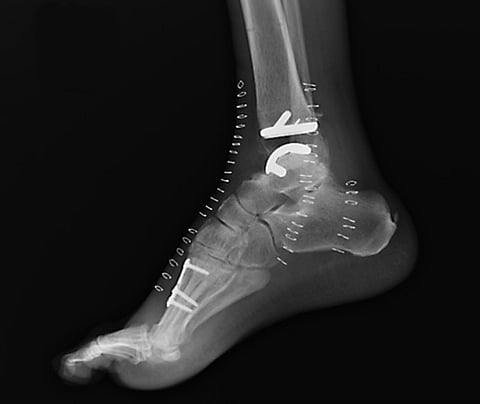

Parekh cut into the front of the ankle and down through the soft tissue all the way to the bone. Then he cut away from both sides of the joint to make way for the implant. He removed enough bone to install two metal pieces and a plastic piece — called the Cadence total ankle replacement — to hold the ankle together and provide it with flexibility. Then he stitched up the repaired joint.